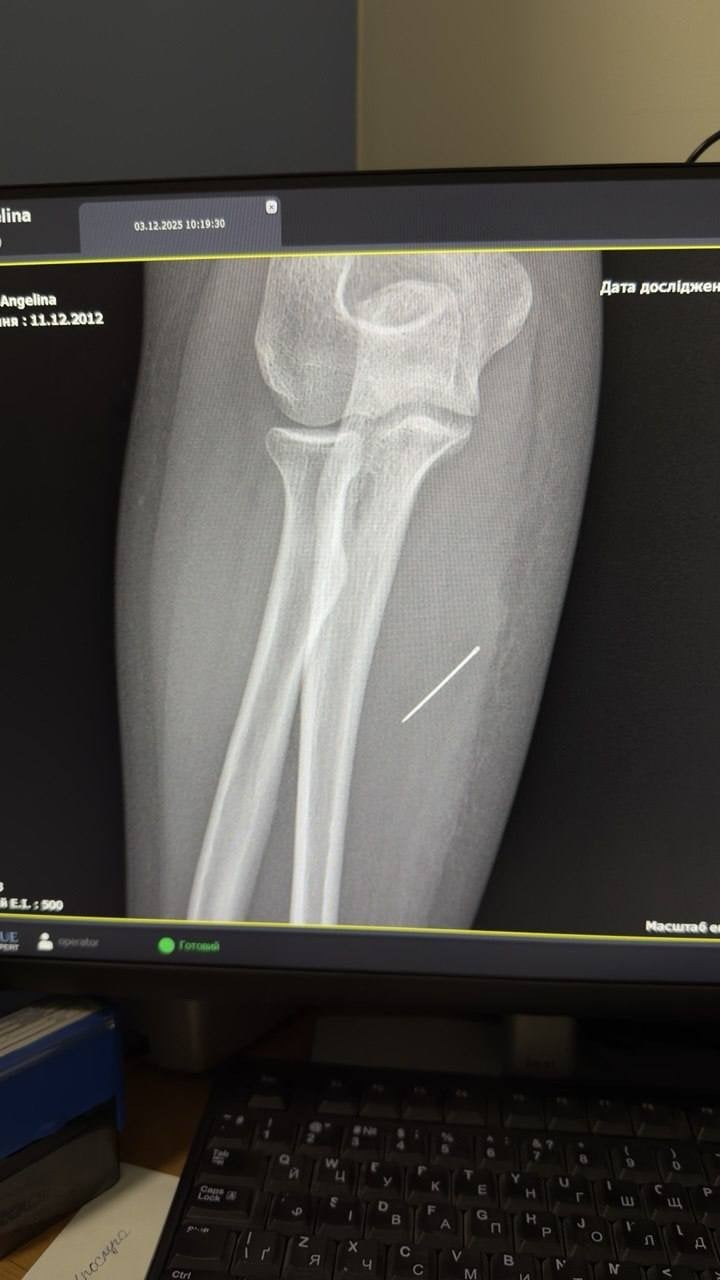

Подальше рентгенологічне дослідження показало, що голка проникла в м’які тканини під кутом 45 градусів і застрягла глибоко в товщі м’яза. За словами лікарів, у разі подальшої міграції металевий предмет міг пошкодити судини або нервові закінчення.

Під час операції хірурги використали рентген-навігацію (ЕОП), що дозволило точно визначити місце знаходження голки та витягнути її по траєкторії входження, не допустивши зламу. Операція пройшла успішно.